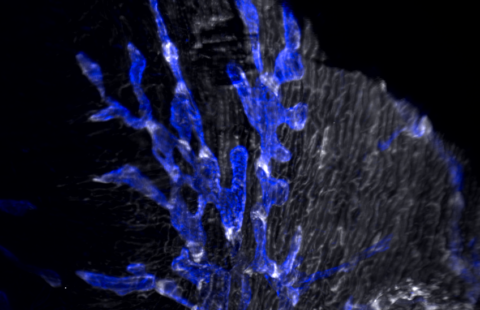

Microscopie électronique d’une cellule infectée par le SARS-CoV-2 © Philippe Roingeard, Anne Bull-Maurer, Sonia Georgeault, unité Inserm U1259 MAVIVH & Université de Tours, France.

© Guy Gorochov